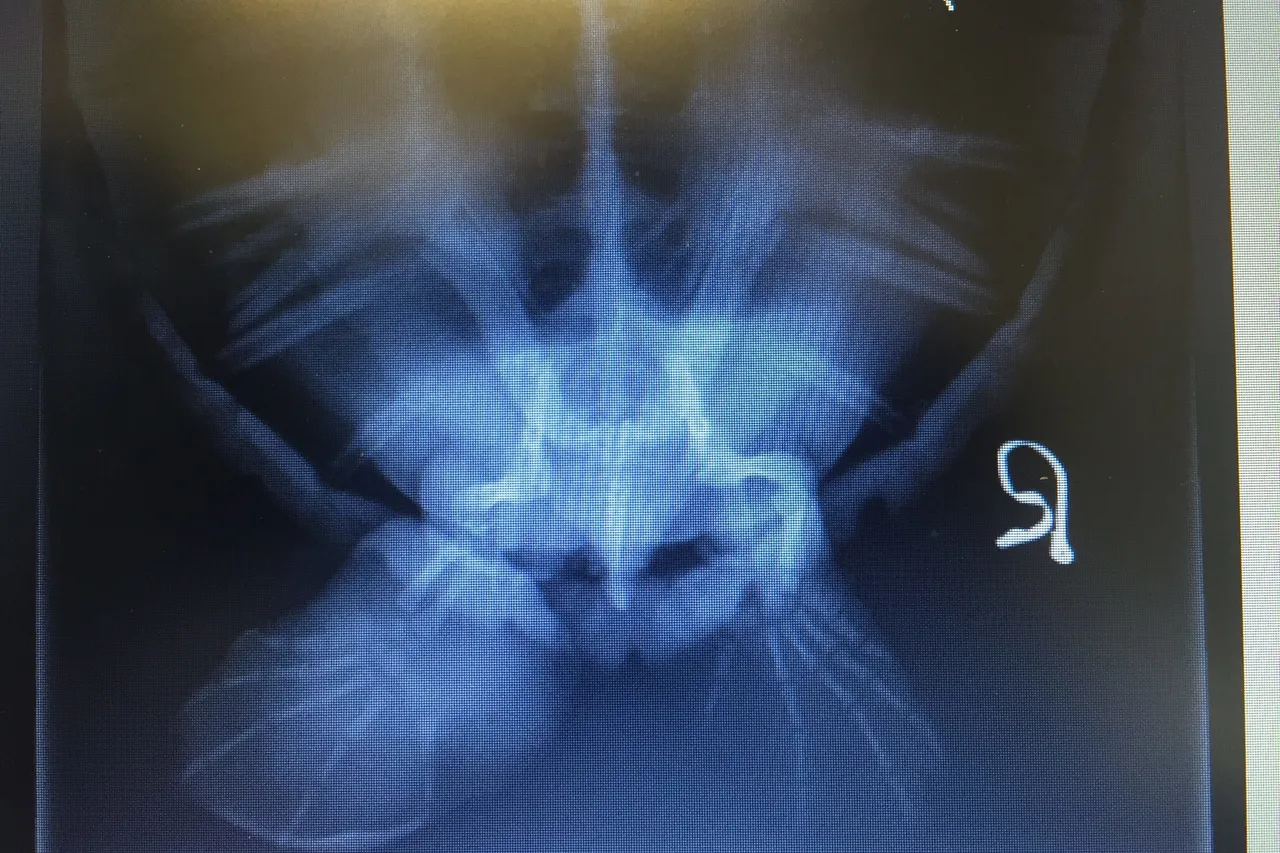

A postmortem examination was conducted on Marcel the turtle, to determine the cause of death, and it was found that his gut was already necrotic - the infection had already spread from his flipper and the damage was too extensive for this turtle to ever recover.

This autopsy also revealed another sad problem - Marcel's stomach contained 67 pieces of plastic - bits of hard microplastic, pieces of rope, clothing fibres and plastic shopping bag fragments. Although ingested plastic was not the cause of death in the case of Marcel, the sheer quantity of plastic we found was alarming. These must have been fragments of plastic that he had consumed along the South African coastline before becoming entangled in the ghost fishing net.